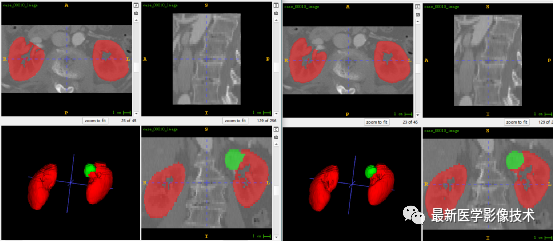

5、验证集分割结果

左图是金标准结果,右图是预测结果。